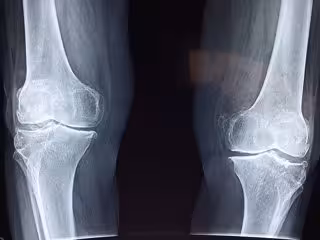

Radiografía de rodilla.

Radiografía de rodilla. - PIXABAY/ TAOKINESIS - Archivo